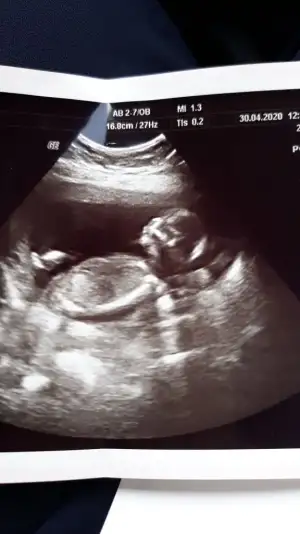

Kaç haftalık 11 12 13 hafta olmalı sanki buyuk usg tekrar usg paylaşırsınız sanki kız gibi

O usg de 16 haftalikti malesef sizin dediginuz hafyalarda gidemedim salgin yuzundenKaç haftalık 11 12 13 hafta olmalı sanki buyuk usg tekrar usg paylaşırsınız sanki kız gibi

Sanki kız gibi geldi bana dr söylemedimiO usg de 16 haftalikti malesef sizin dediginuz hafyalarda gidemedim salgin yuzunden

Yok dr bisey demedi goremiyorum dediSanki kız gibi geldi bana dr söylemedimi